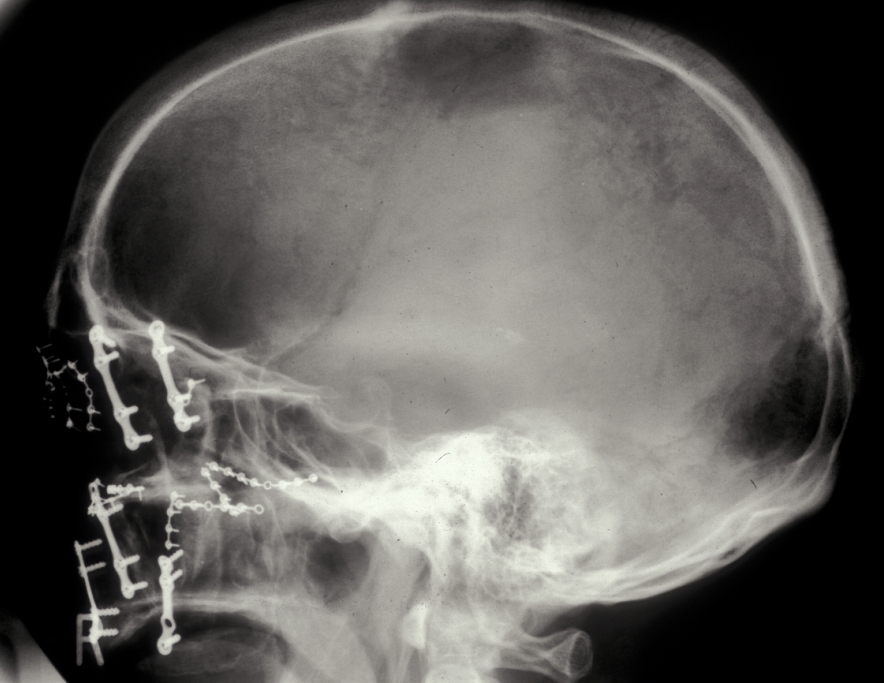

In the region of the angle of the mandible, a single plate is adequate to allow healing. In practice many surgeons now supplement this (or even replace it) with a transbuccally placed lateral plate which prevents lateral displacement of the lower border of the mandible. All these techniques use monocortically placed matching titanium screws to retain the plates which immobilise the fracture sites. Long-acting local anaesthetic regional block provides good postoperative analgesia and prophylactic broad-spectrum antibiotics are given preoperatively. Intraoral wounds are closed with resorbable sutures. If the occlusion is fully restored and stability of the fracture is assured by the plates, the intermaxillary fixation can be removed. Postoperative radiographs are taken to ensure correct placement of plates and screws and accurate realignment of mandibular fragments. It is also important to reassess the position of the condyles following ORIF as malpositioning can lead to TMJ problems later on (see Figure 5).

Condylar fractures: these are the most common mandibular fractures. They are treated conservatively in children up to 12 years with soft diet, analgesia and function. Young adults (12-18) are also treated conservatively in the majority of cases. Adults (>18) are treated with 7-10 days of heavy elastic IMF (fixation) and the occlusion reassessed. If malocclusion persists then ORIF of the condyle is undertaken. Overlap of fragments greater than 5 mm and angulation greater than 37°are postulated to warrant ORIF. Logically the function rather than the radiographic appearance should predicate the decision to undertake ORIF (see Figure 9 and Figure 10 for illustration).